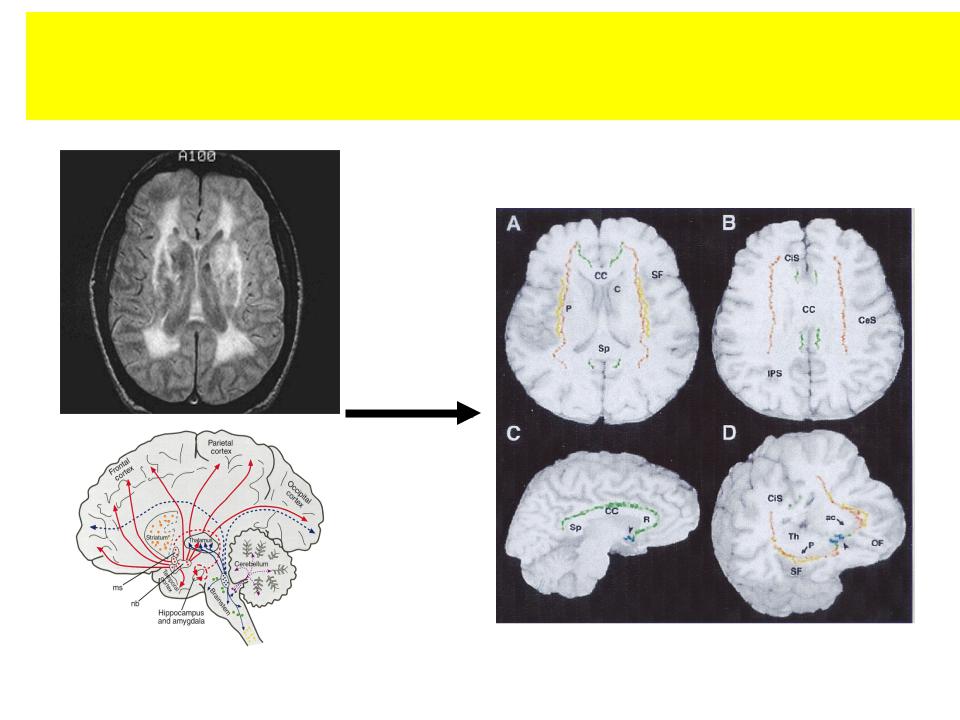

Поражение холинергических путей при сосудистой деменции